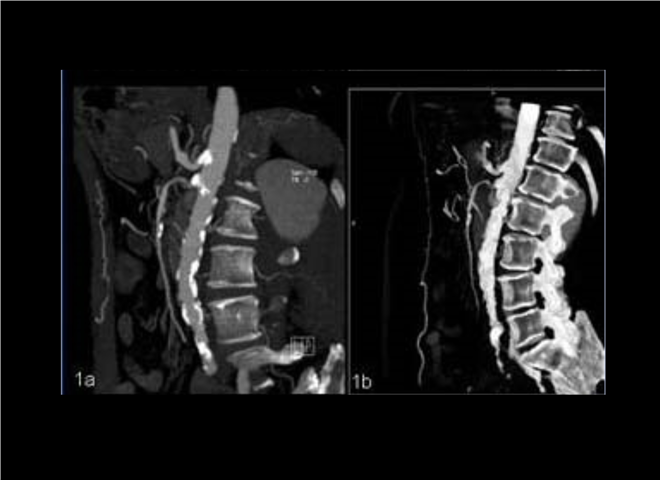

13_CT增强扫描